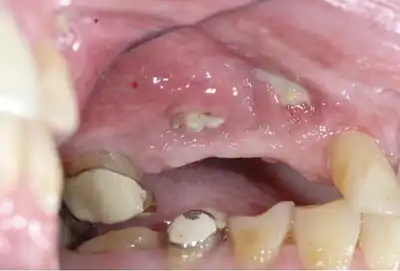

| Osteonecrosis of the jaw of the upper left jaw in a patient diagnosed with chronic venous insufficiency | |

Osteonecrosis of the jaw (ONJ) is a severe bone disease (osteonecrosis) that affects the jaws (the maxilla and the mandible). Various forms of ONJ have been described since 1861, and a number of causes have been suggested in the literature.